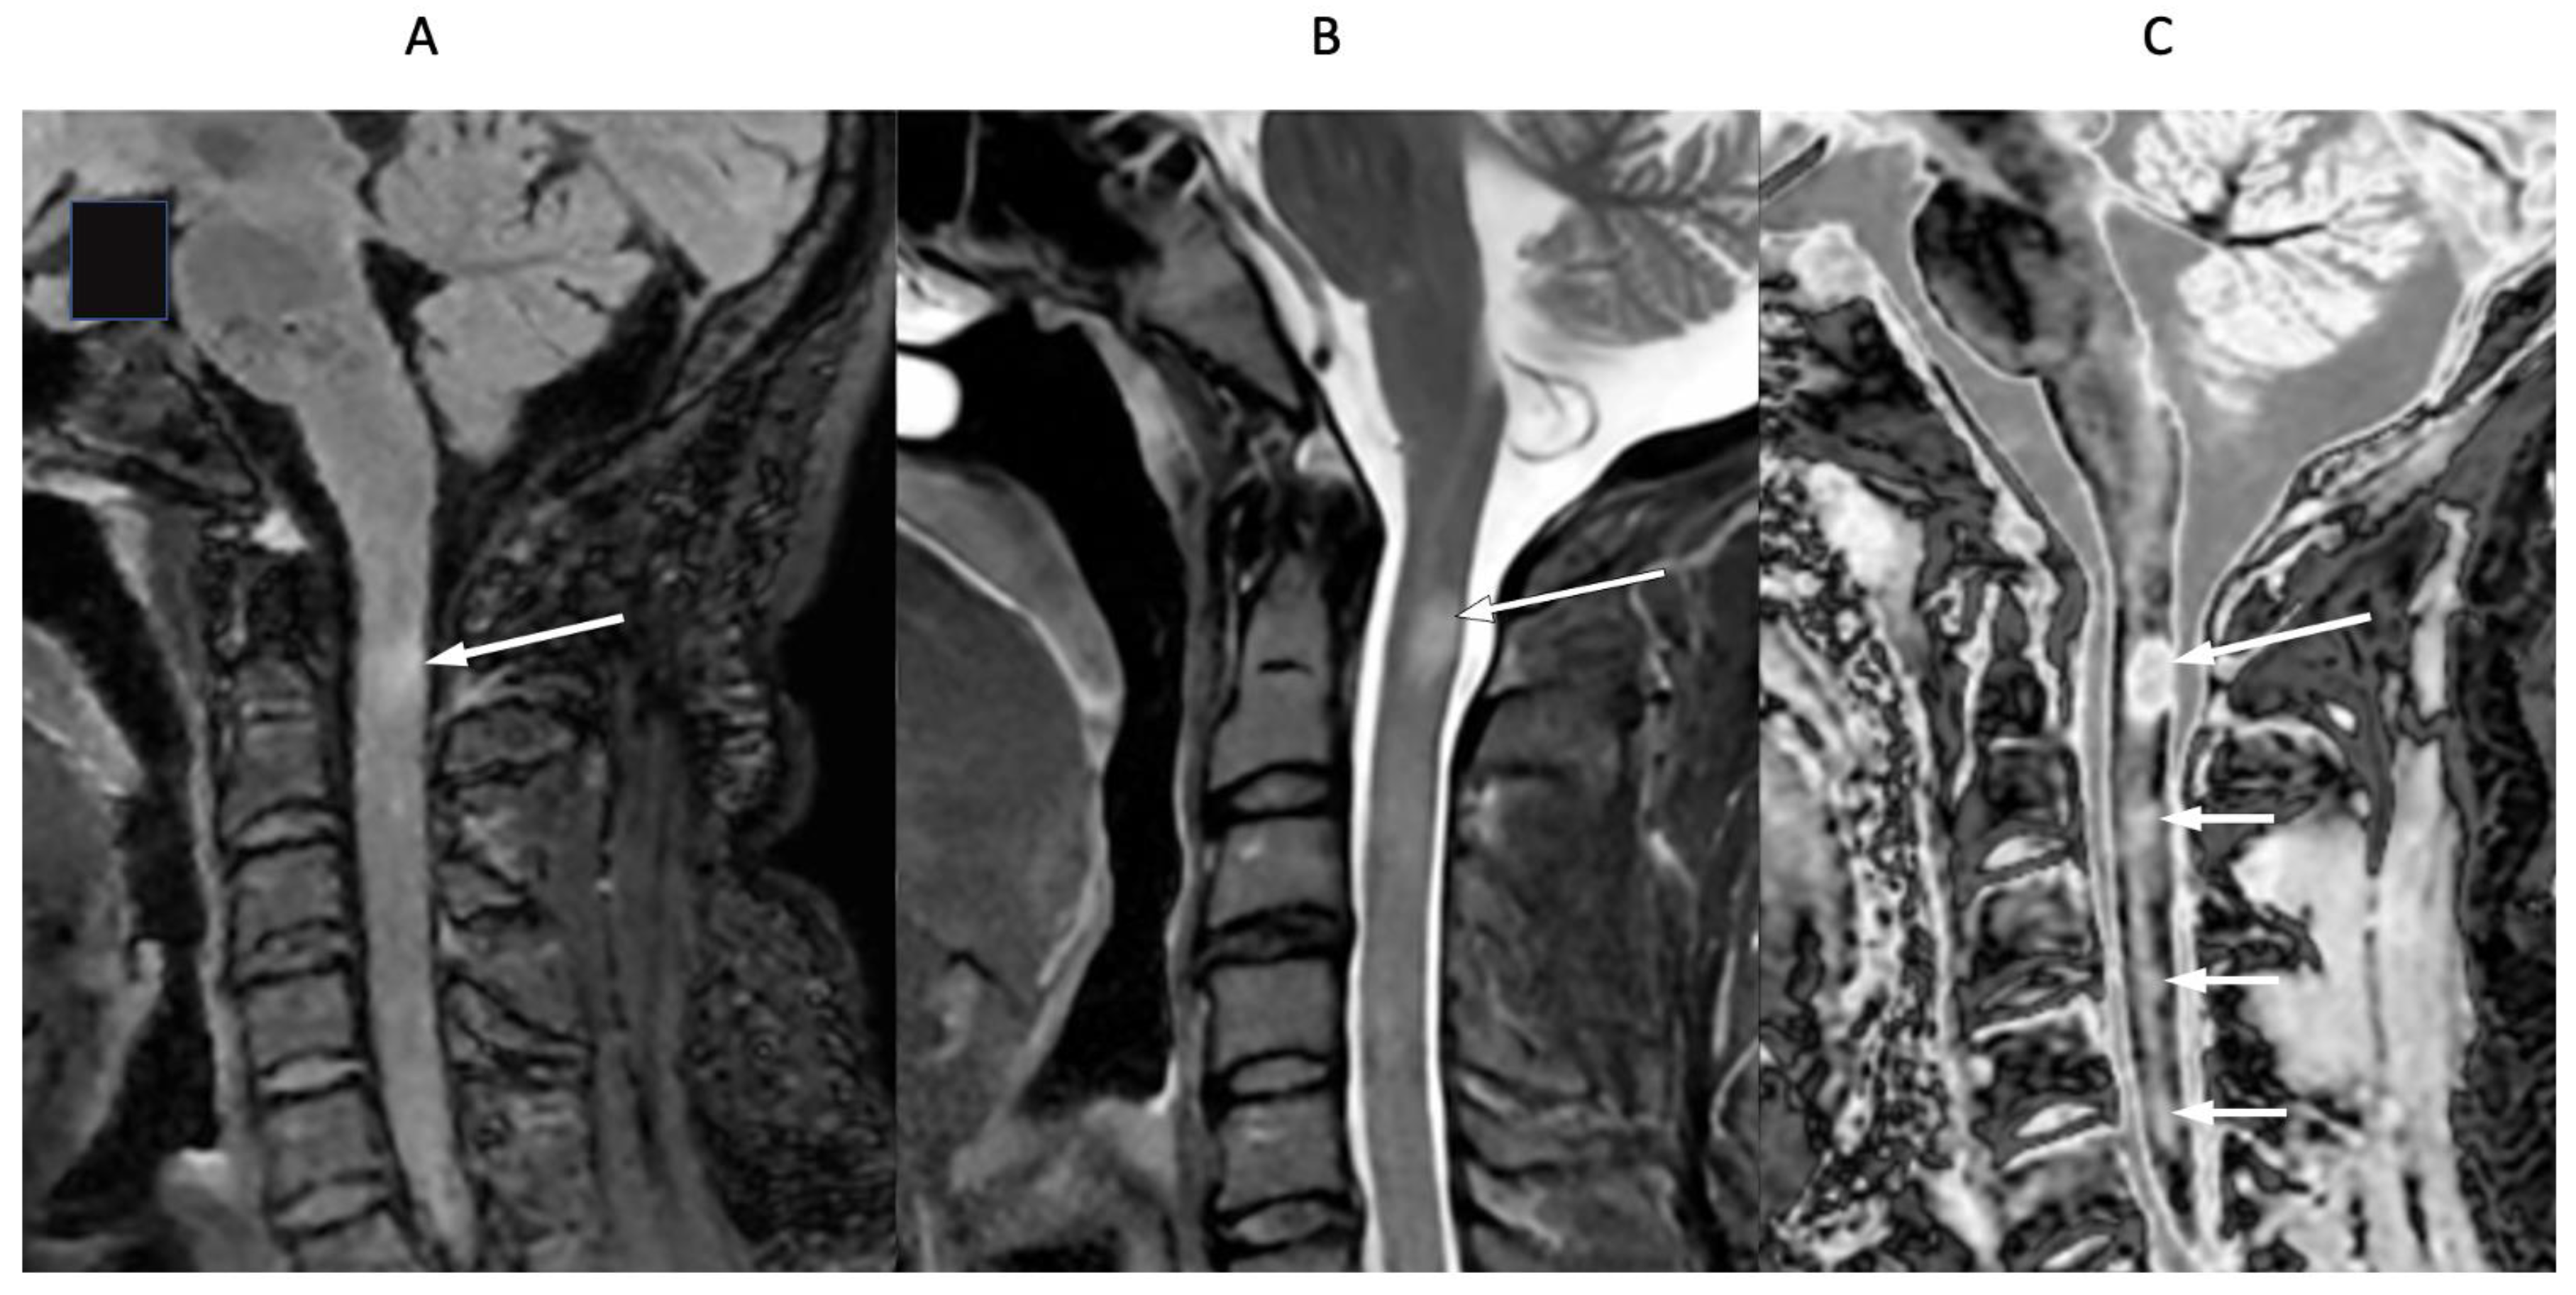

4. Illustrative Cases